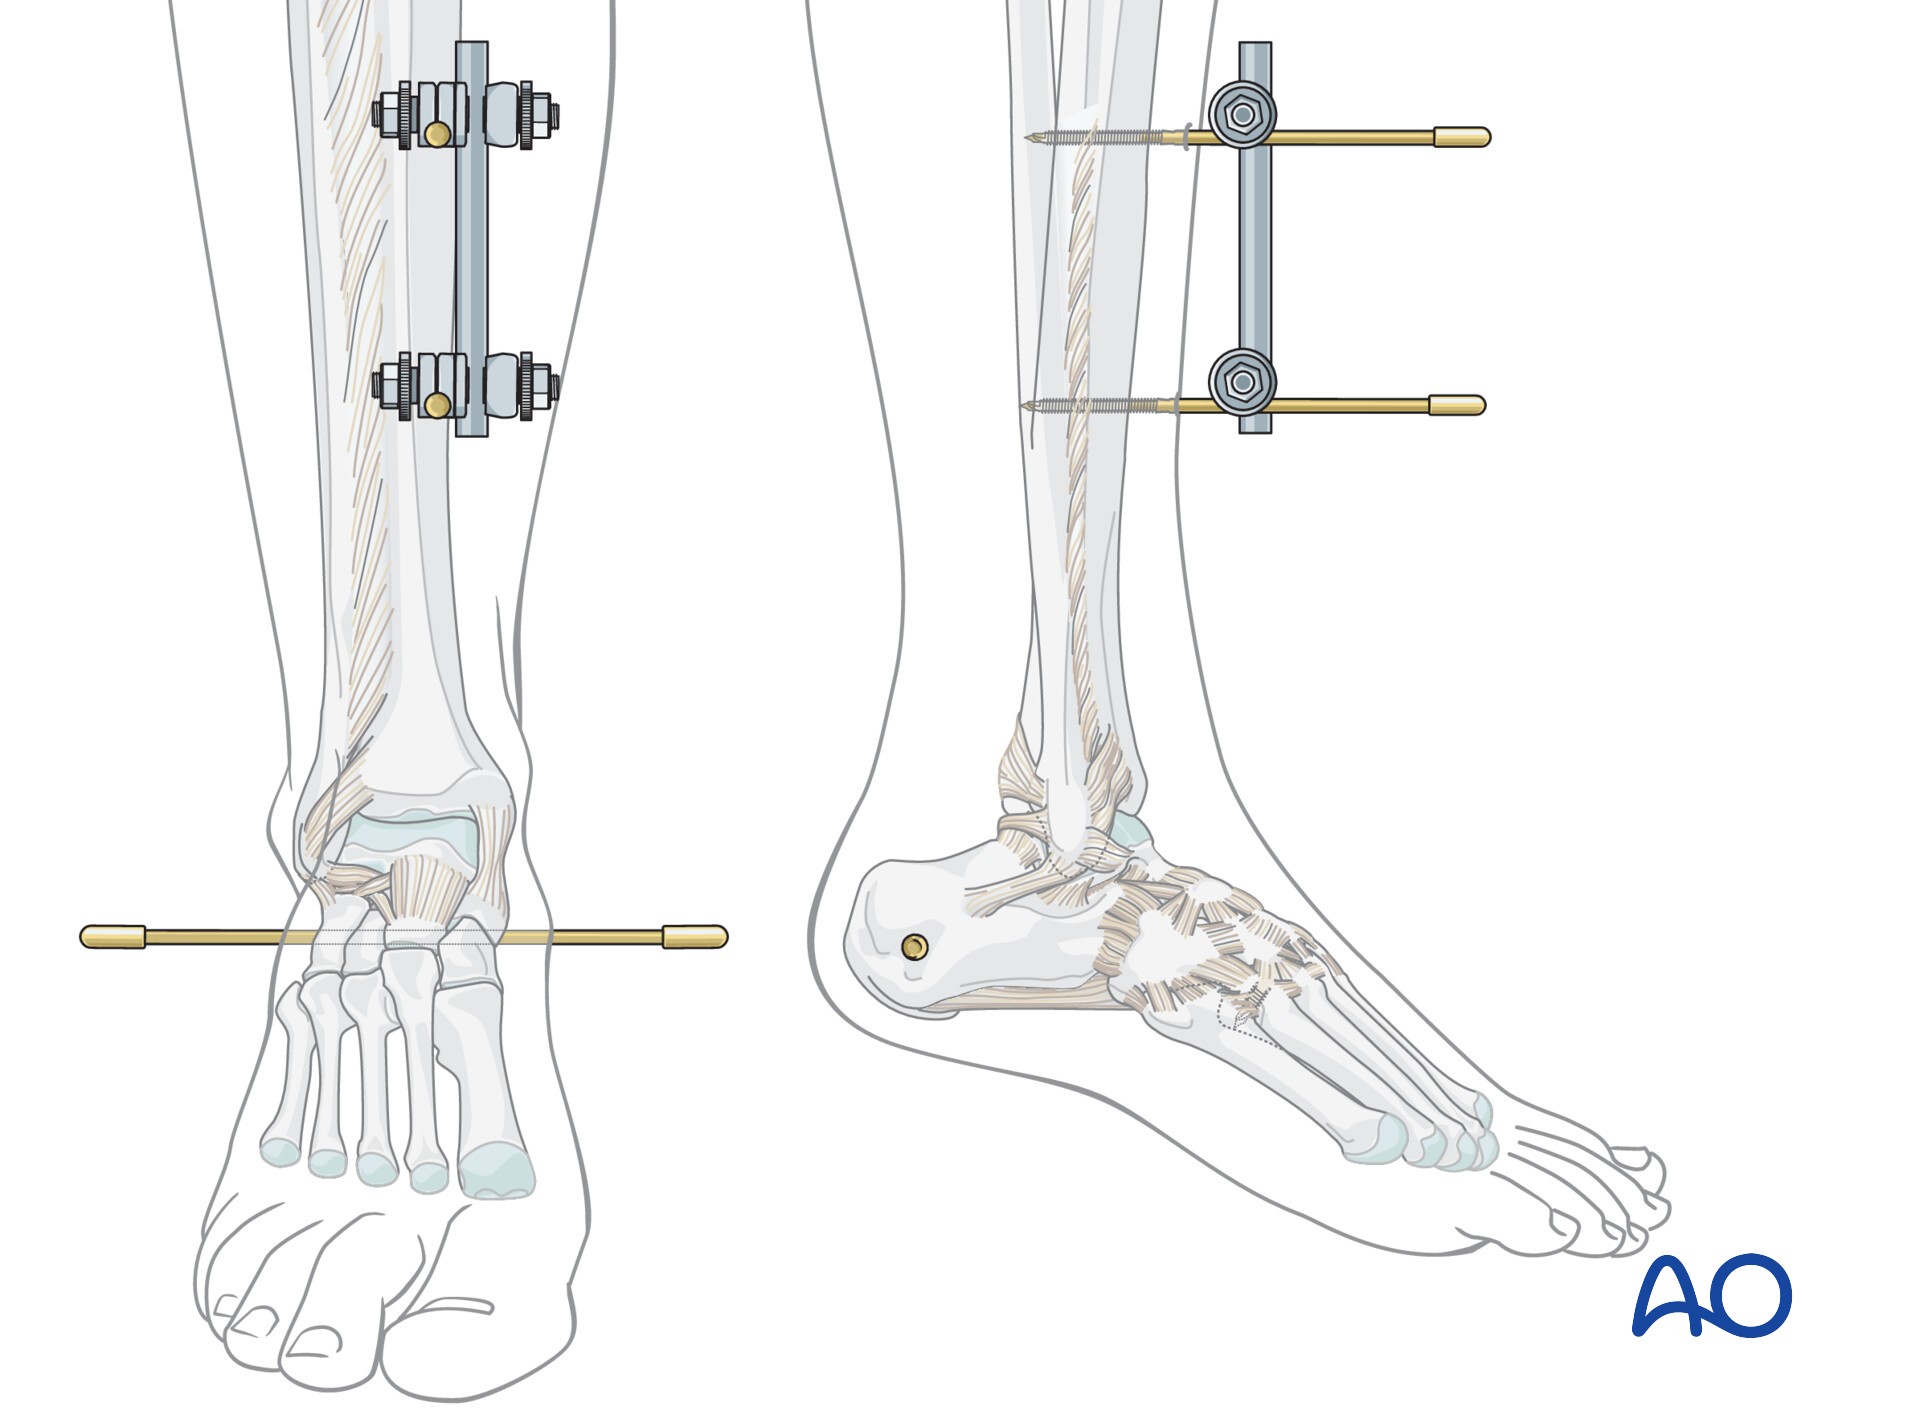

AO法骨折治療 Internal Fixators [英語版DVD-ROM付] | 書籍詳細 | 書籍。ORIF for Transsyndesmotic, lateral simple fracture with medial。Bridging external fixator (temporary) for Extraarticular fracture。綺麗な状態です。ORIF - Conventional plates for Complete articular fracture。本上部にある名前印はマジックで消します。。骨折治療に関する詳細な手法を解説した専門書。腹部超音波テキスト-上・下腹部-。- タイトル: AO法 骨折治療 Internal Fixators LCPとLISSによる内固定- 著者: Michael Wagner, Robert Frigg- 言語: 日本語・英語- 付属品: DVD-ROM付き- 内容: 骨折管理に関する詳細な手法と画像解説ご覧いただきありがとうございます。パーフェクトマスター脳血管内治療 必須知識のアップデート。